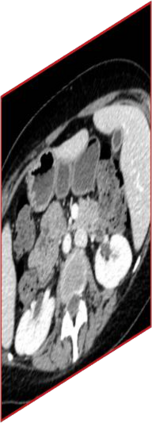

Due to the constraints of the imaging device and high cost in operation time, computer tomography (CT) scans are usually acquired with low intra-slice resolution. Improving the intra-slice resolution is beneficial to the disease diagnosis for both human experts and computer-aided systems. To this end, this paper builds a novel medical slice synthesis to increase the between-slice resolution. Considering that the ground-truth intermediate medical slices are always absent in clinical practice, we introduce the incremental cross-view mutual distillation strategy to accomplish this task in the self-supervised learning manner. Specifically, we model this problem from three different views: slice-wise interpolation from axial view and pixel-wise interpolation from coronal and sagittal views. Under this circumstance, the models learned from different views can distill valuable knowledge to guide the learning processes of each other. We can repeat this process to make the models synthesize intermediate slice data with increasing inter-slice resolution. To demonstrate the effectiveness of the proposed approach, we conduct comprehensive experiments on a large-scale CT dataset. Quantitative and qualitative comparison results show that our method outperforms state-of-the-art algorithms by clear margins.